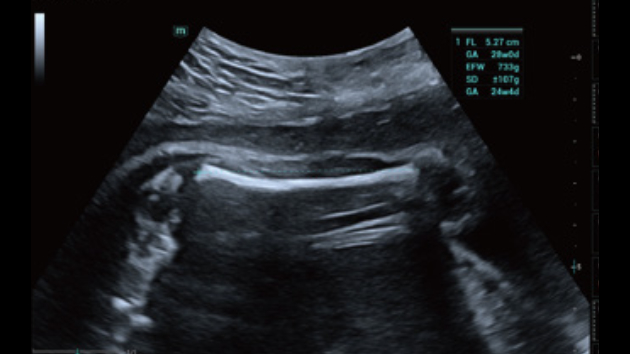

The Consona features new and concrete solutions, that efficiently help you to carry out smooth diagnoses for extensive type of patients.

No matter your routine is in hospitals, clinics, or you are honing skills in General Imaging applications, women's health care or cardiovascular specialties, you will find highly powerful tools available on this series to keep you stay ahead.